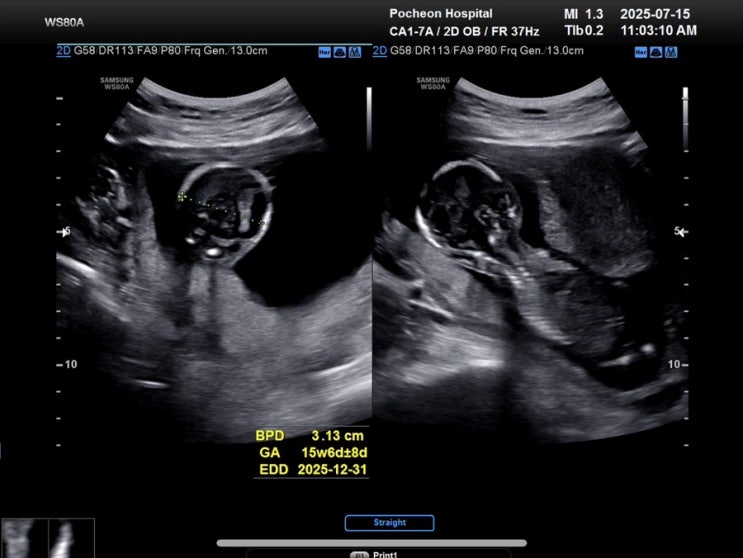

포천의료원 16주차 기형아검사

첫째 키우다 보니 어찌저찌 1년만에 다시 쓰게 되따-! 이번에는 둘째—- 두둥! 어쩌다 연년생을… 쨋든 그...